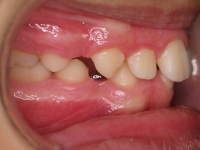

La paciente O.O. acude a nuestra consulta por:

– Canino 13 e incisivo lateral 42 en posición ectópica.

– Canino 23 incluido.

Con lo que decide realizarse un tratamiento de ortodoncia de duración de 24 meses con brackets damon Q.

CASO COMPLETO: